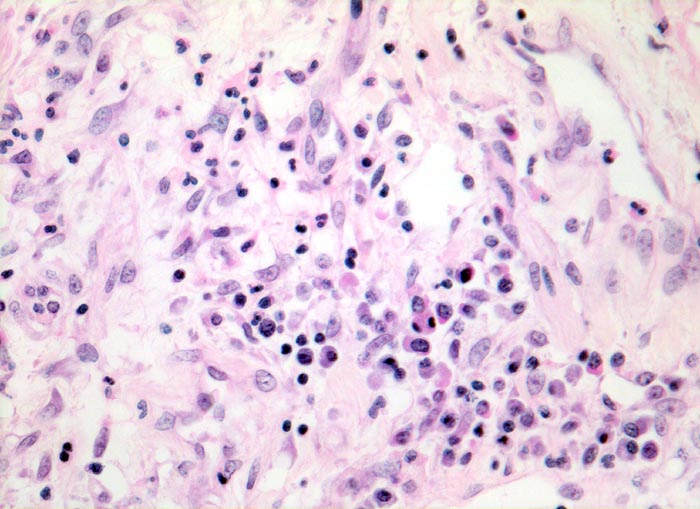

Diffuser Alveolarschaden: proliferative Phase

Stark verbreiterte Alveolarsepten mit Fibroblastenproliferaten, Gefässeinsprossungen und gemischtem Entzündungsinfiltrat aus Lymphozyten, Histiozyten und Granulozyten.

Makroskopischer Lungenbefund: schwere, wässrige und verfestigte dunkelrote Lungen aus denen sich nur wenig Flüssigkeit auspressen lässt.

Hospitalisation wegen akuter nekrotisierender Pankreatitis. Am zweiten Hospitalisationstag entwickelt der Patient ein ARDS (Adult Respiratory Distress Syndrome) mit rasch progredienter Dyspnoe und Tachypnoe, sowie einer Hypoxämie, welche im Verlauf auf Sauerstoffgabe nicht mehr anspricht. Das Thoraxröntgenbild zeigt bilaterale diffuse Verschattungen. Der Patient verstirbt trotz Intensivmassnahmen am 9. Tag nach Spitaleintritt am Multiorganversagen.

Histologie

320